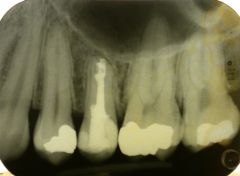

Caso iniziale. Si notino la lesione periapicale, la radice raccorciata per il riabborbimento dell'apice radicolare e l'area di riassorbimento interno nel terzo apicale della radice.

La paziente giunge all'osservazione con viso tumefatto. All'ispezione intraorale anche la gengiva dei denti del secondo quadrante appariva tumefatta e violacea, di consistenza molle. La diagnosi di ascesso periapicale è stata piuttosto semplice. Il dente all'origine del problema era il secondo premolare sinistro. Radiograficamente il dente mostrava una grande lesione periapicale granulomatoide, una evidente rizolisi apicale ed un'area di riassorbimento interno. Il dente è stato aperto per favorire un drenaggio. Successivamente è stata intrapresa una procedura di apecificazione che ha richiesto circa due anni. Durante questi due anni il dente è stato periodicamente medicato con idrossido di calcio e controllato radiograficamente. In questo intervallo di tempo la lesione periapicale si è pressoché completamente riassorbita. A questo punto il dente è stato chiuso definitivamente con guttaperca e root canal sealer. Con il tempo è stato possibile osservare la scomparsa della lesione periapicale ed un successo endodontico che ad oggi ha compiuto 10 anni.